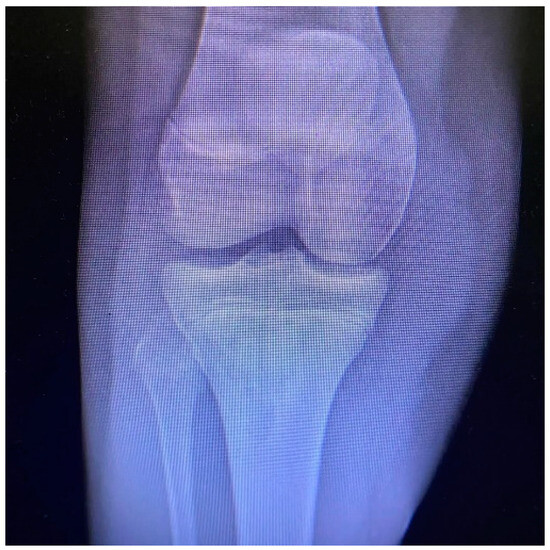

Tibial Tubercle Avulsion Fracture in Young Athletes Surgically Treated: Mid-Long Term Result and Comparison

1. Introduction